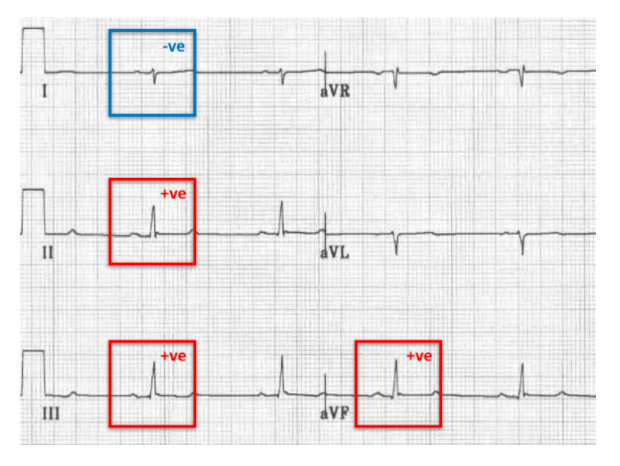

What does a posterior division hemiblock cause on an ECG?

Right axis deviation